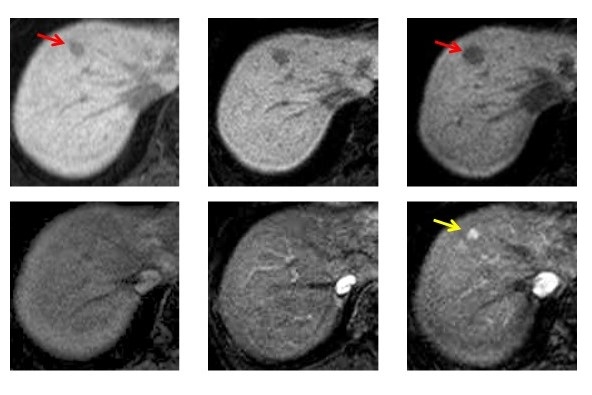

肝細胞癌の早期発見・早期診断のために私たちはあらゆる努力をしています。肝臓が「沈黙の臓器」であるのは癌ができた時も同じで、しっかりした治療が可能な肝がんの大きさでは本人に症状はなく、症状が出てから癌が見つかるのではほぼ手遅れです。肝癌の早期発見にはまず画像検査、特に日常外来で行える腹部超音波検査が基本です。これで肝臓の腫瘍が疑われたり、超音波で十分な観察ができない場合にはCTやMRI検査を行います。特に最近ではMRI検査では、特殊な造影剤を用いてまだ肝細胞癌になる前の、非常に早期な腫瘍を見つけることが可能です(図3)。

図3:MRI検査でみられる、非常に早期な腫瘍(赤い矢印)の肝細胞癌(黄色の矢印)への進行